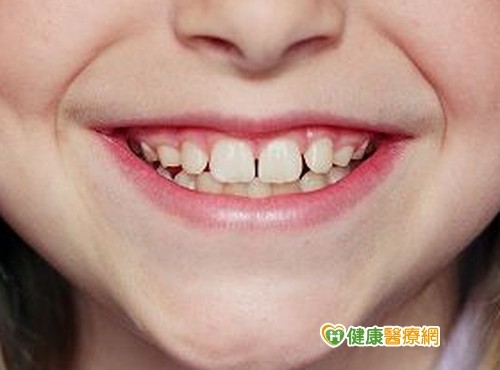

Иллюстрации флюороза молочных зубов